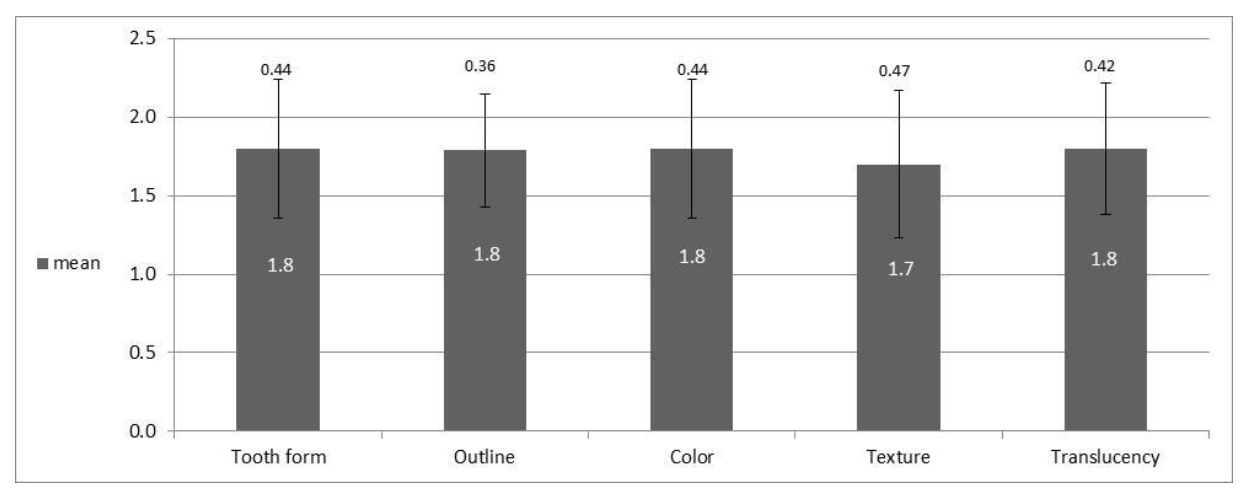

- The shape of the original tooth;

- Outline and volume of the clinical crown;

- A color that includes the evaluation of hue and value indices;

- Surface texture;

- Transparency and characterization.

3.4. Analysis of Esthetic Results by Index: WES

| Mean | 1.7 | 1.8 | 1.9 | 1.8 | 1.8 | 9 | 1.8 | 1.8 | 1.8 | 1.7 | 1.8 | 8.8 | 17.8 | |